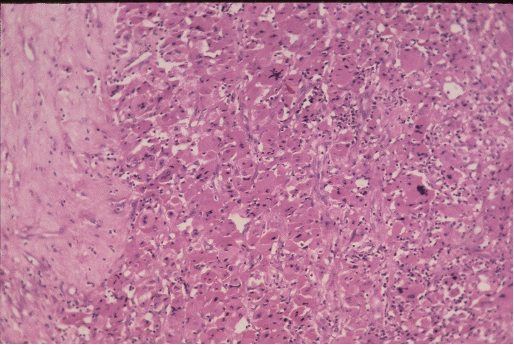

A 55 year old male patient presented with a mass in the

lumbar region, found to be at ultrasound in the renal/suprarenal position. Excision was done and the appearances are shown in fig 1 & 2 . Make you diagnosis. What could be the differentials?

Fig 1

Fig 2